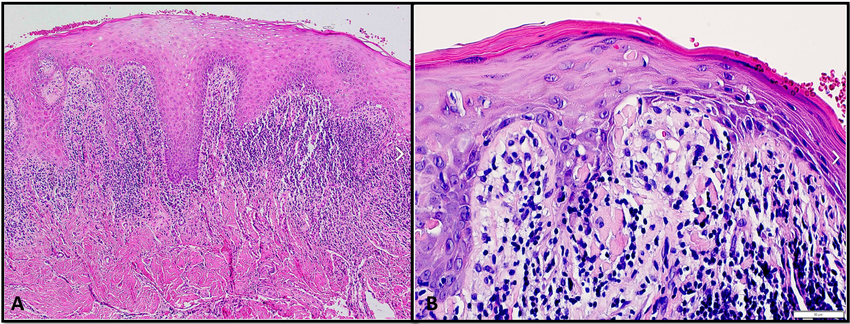

Histopathology: Interface dermatitis with a band-like (lichenoid) lymphocytic infiltrate at the dermoepidermal junction. Civatte bodies (colloid/apoptotic bodies) in the lower epidermis. "Saw-tooth" pattern of irregular acanthosis.

A) Lichen planus shows saw tooth rete ridges and B) Colloid bodies.